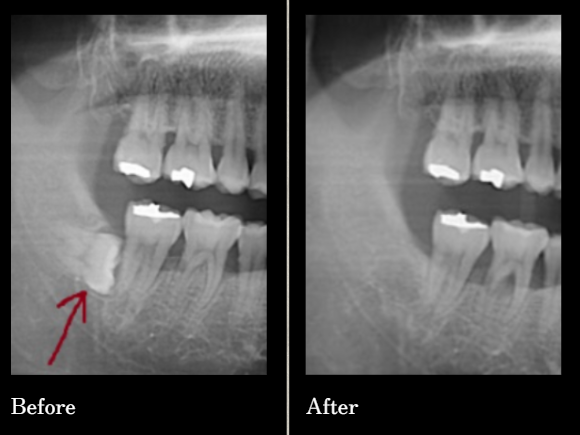

수많은 환자의 경험과 신뢰로 증명된

연세원치과 사랑니 발치입니다.

*위 케이스는 본원에서 진행 받으신 분의 동의 후 동일한 촬영 조건에서 촬영한 사진을 사용하였습니다.